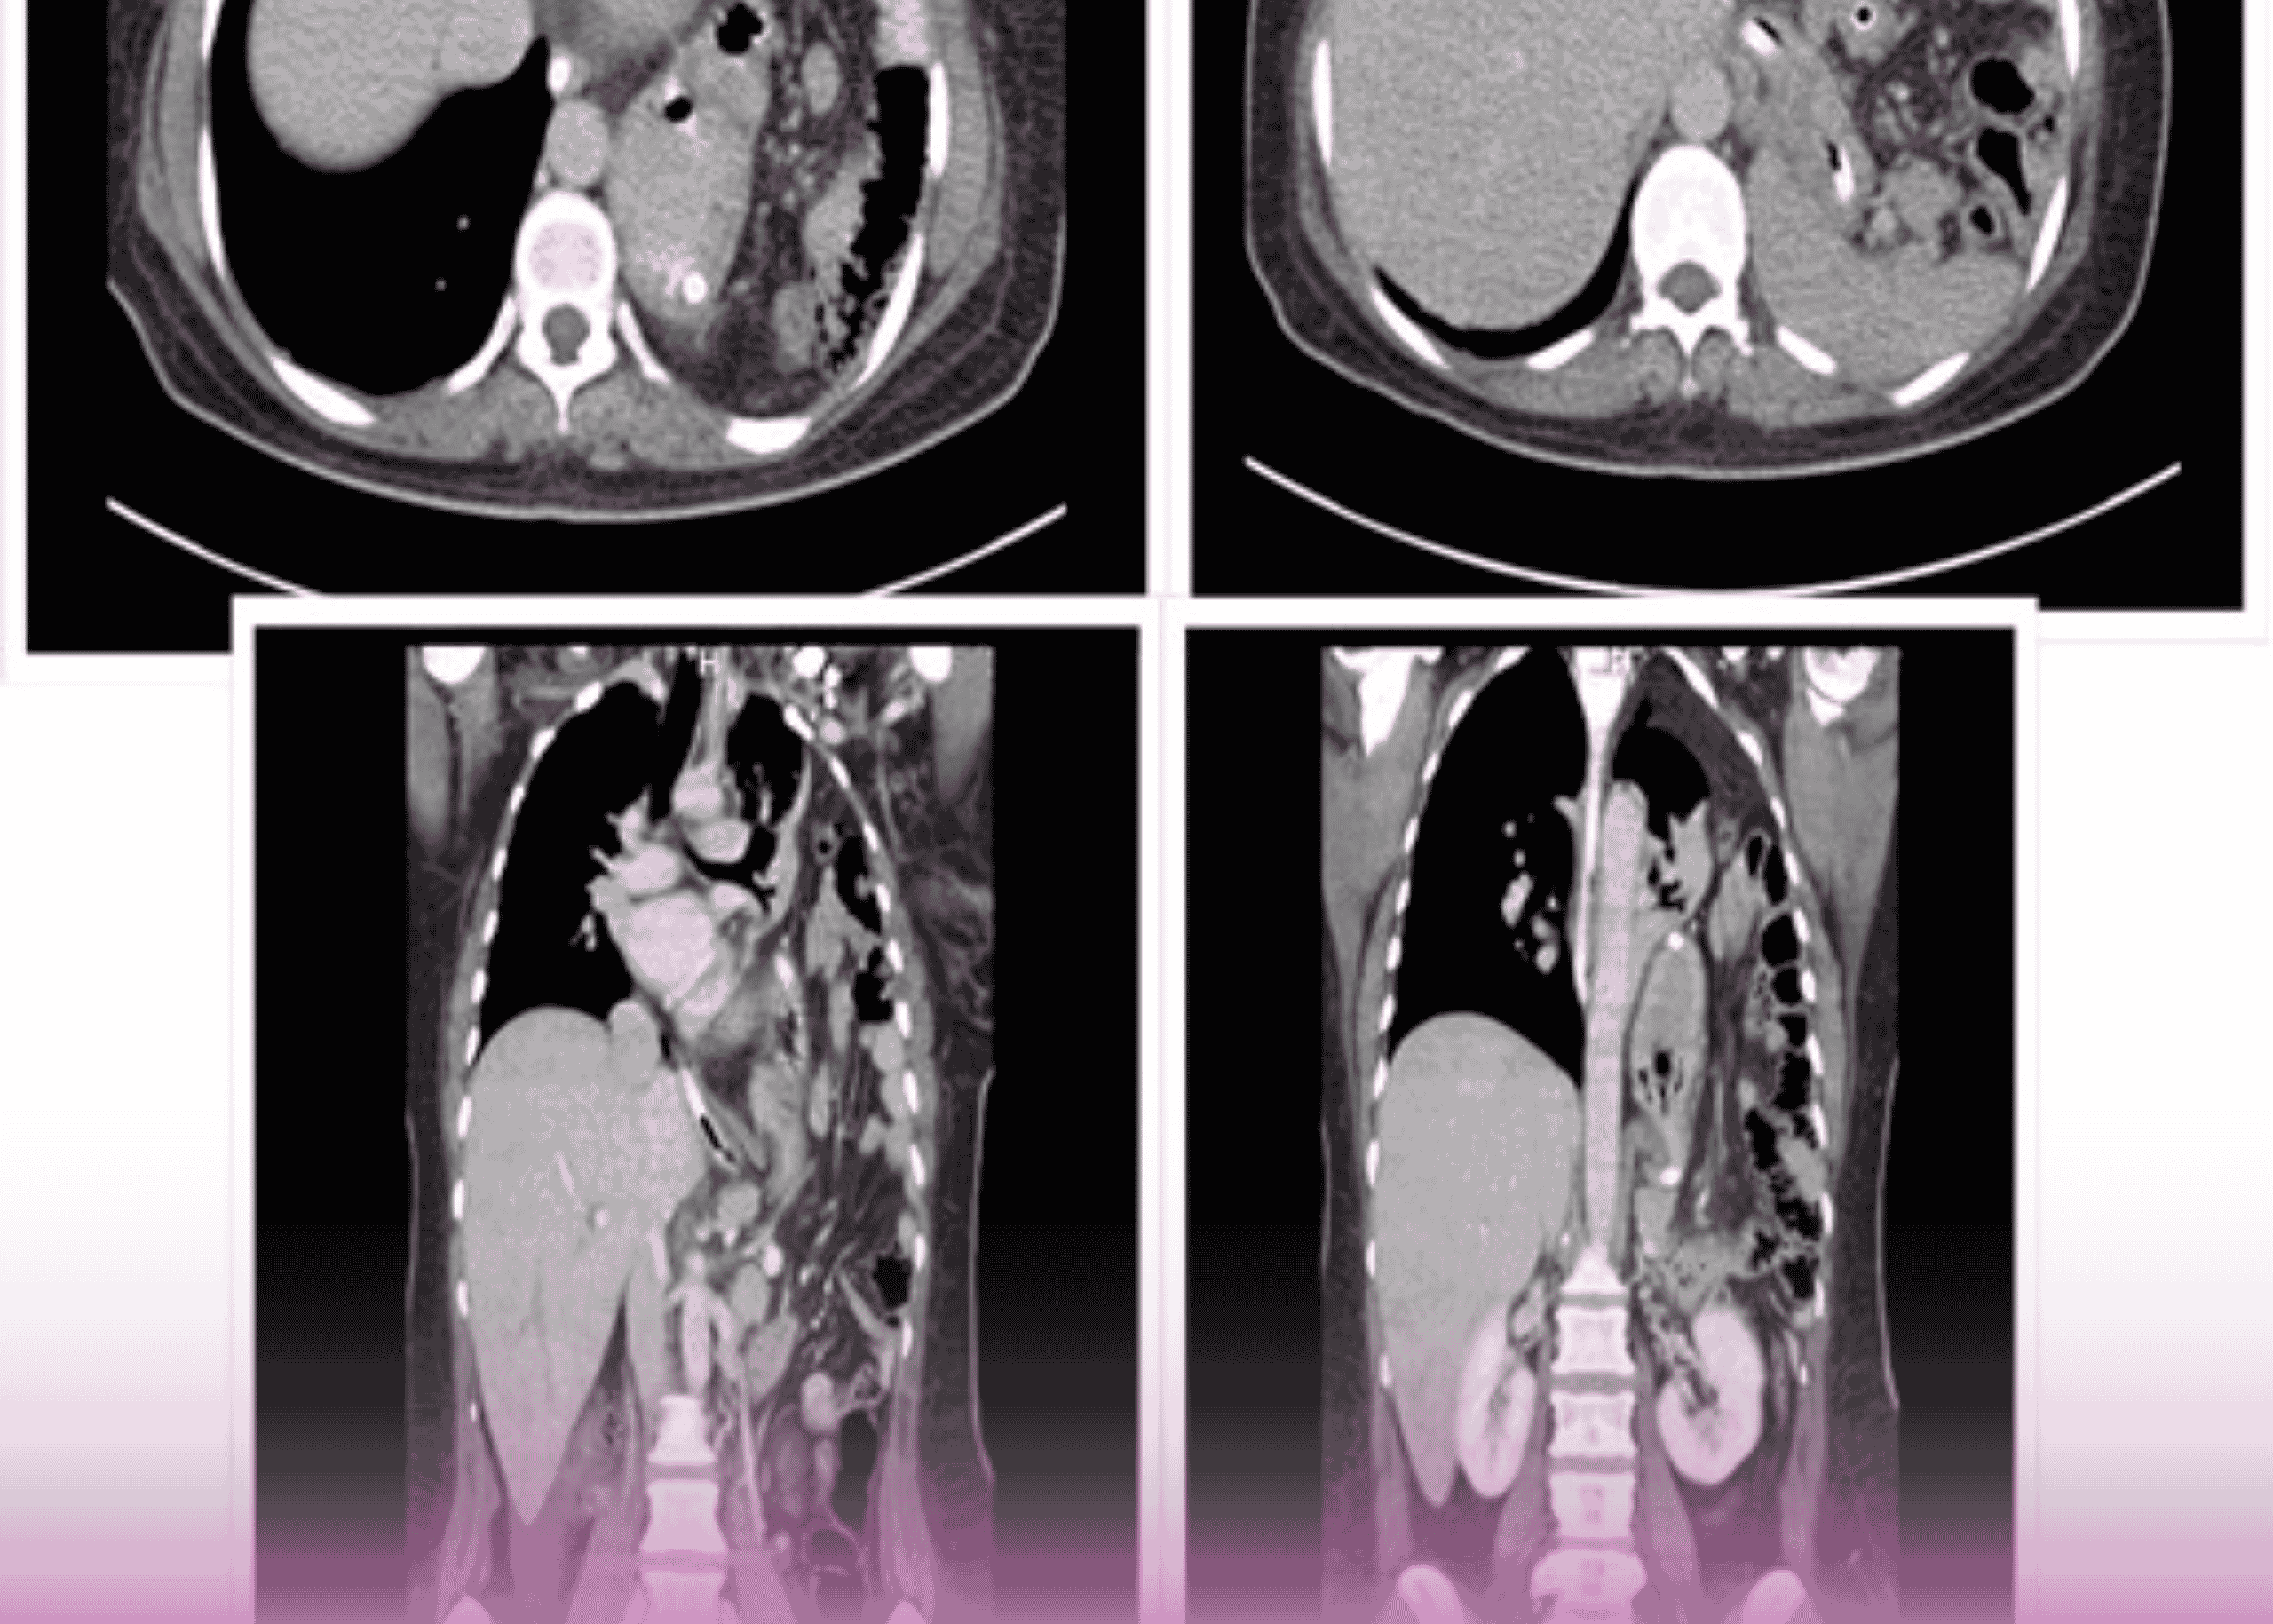

فتق الحجاب الحاجز ما بعد الرضح: التدبير الجراحي لحالة معقدة باستخدام المدخل الصدري البطني

مقدمة تمثل الفتوق الحجابية تحدياً جراحياً كبيراً، خاصة عندما تكون كبيرة وتحتوي